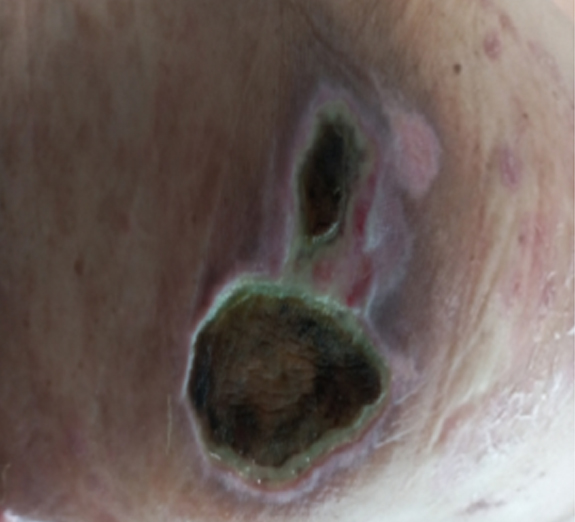

3단계욕창 (심부 조직 손상)

• 피하조직, 지방층까지 손상

• 괴사 조직이 보일 수 있음

치료 방법

• 성형외과 전문의에 의한 상처 평가

• 괴사 조직 제거(변연절제술)

• 전문 창상 드레싱 및 감염 치료

• 전신 상태(영양, 빈혈) 동시 관리

심부욕창 치료 사례

• 치료 전

• 치료 후